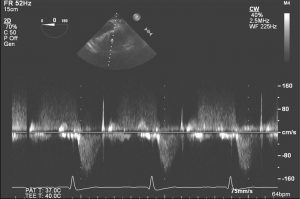

🎥4️⃣: The deep transgastric position at zero degrees can be used to assess for valve gradients by TEE. Here is a typical view. Color doppler shows there is some mild valvular regurgitation.